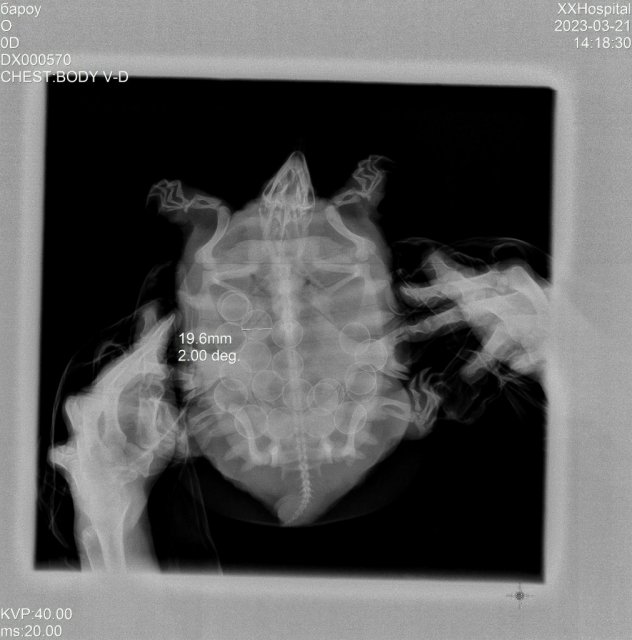

Suppon Ваше имя: Калина Локация: Набережные челны Опубликовано: 30 мая 2024 Опубликовано: 30 мая 2024 г. Набережные Челны (Татарстан), 22 года. Китайский трионикс. Аквариумное содержание. Размер 1200х600х600. Аквариум наполнен наполовину (200-250 литров). Оборудование: внешний фильтр Эхейм Професионал 4+ (на 350л, прокачка 1200 л/час), обогреватель Барбус (300 л), лампа Репти Зоо (BeamSpot Lamp) 50W UVA , лампа Репти Зоо (Desert T8 UVB 10,0). Лампа накаливания: Репти Зоо (BeamSpot Lamp) 50W UVA. Работает 10 часов в день. Ультрафиолетовая лампа: лампа Репти Зоо (Desert T8 UVB 10,0). Работает 10 часов в день. Работает 1 год, под замену. Берега нет. внешний фильтр Эхейм Професионал 4+ (на 350л) Грунт - крупная гладкая галька с ракушечником. Температура: 20 - 24 С. Корм: рептомин, камбала, хек. Кальций при каждом кормлении. Кормление раз в два-три дня. Возраст: 4 года. Вес примерно 1,3 Сегодня заметила, что из пасти черепахи пошла кровь. Немного покровило и остановилось. Порезы на губах не заметила, поэтому предположила, что кровь шла из глотки. Черепаха отказывается от пищи. Три недели назад она отложила одно яйцо и перестала есть. Поведение не поменялось: черепаха активная, при плавании на бок не заваливается. Опускается на дно. Иногда пускает пузыри изо рта. Беспокойство её головка не вызвала, т.к. в прошлом году было всё тоже самое: после полной кладки она продолжила нормально есть. В прошлом же году обращались к местному экзотологу (клиника Зверополис) из-за выпадения яйцевода. Обратиться к экзотологу сейчас не могу: местный перестал принимать . Сегодняшнее фото и Прошлогодний рентген